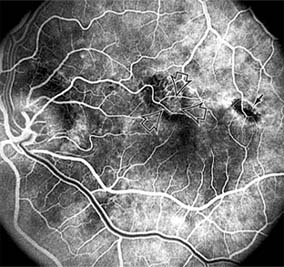

Figure 10-2

Figure 10-2: Central serous chorioretinopathy with sensory retinal detachment (arrows) extending into the fovea.

Figure 10-3

Figure 10-3: Fluorescein angiogram of central serous chorioretinopathy shows active disease with both a retinal pigment epithelial detachment (small arrows) and a sensory retinal detachment (large arrows). Two foci of inactive disease (open arrows) are also present.

Central serous chorioretinopathy is characterized by serous detachment of the sensory retina as a consequence of focal leakage of fluid from the choriocapillaris through a defect in the retinal pigment epithelium (Figures 10-2 and 10-3). This disease typically affects young to middle-aged men and may be related to life stress events. Most patients present with the sudden onset of blurred vision, micropsia, metamorphopsia, and central scotoma. Visual acuity is often only moderately decreased and may be improved to near-normal with a small hyperopic correction.

The diagnosis is made by slitlamp examination of the fundus; the presence of serous detachment of the sensory retina in the absence of ocular inflammation, subretinal neovascularization, an optic pit, or a choroidal tumor is diagnostic. The retinal pigment epithelial lesion appears as a small, round or oval, yellowish-gray spot that is variable in size and may be difficult to detect without the aid of fluorescein angiography. Fluorescein dye leaking from the choriocapillaris may accumulate below the pigment epithelium or sensory retina, resulting in a variety of patterns including the well-recognized smokestack configuration.